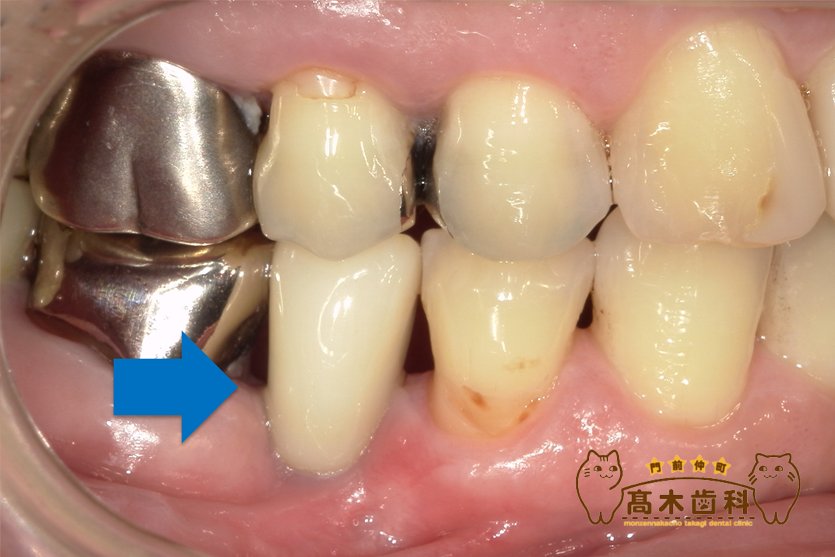

インプラント治療の症例

インプラント埋入手術

症例の詳細はこちら